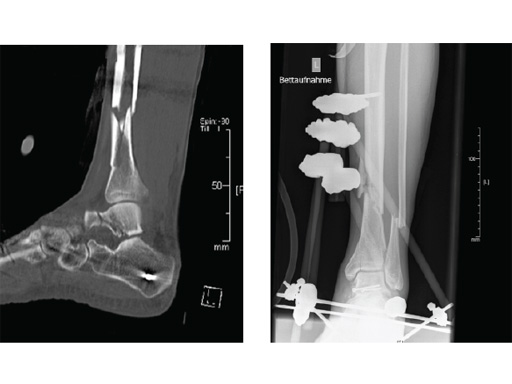

Case provided by Michael Raschke, Münster, Germany

Case 2: Grade II open distal tibial fracture in a polytraumatized 52-year-old man.